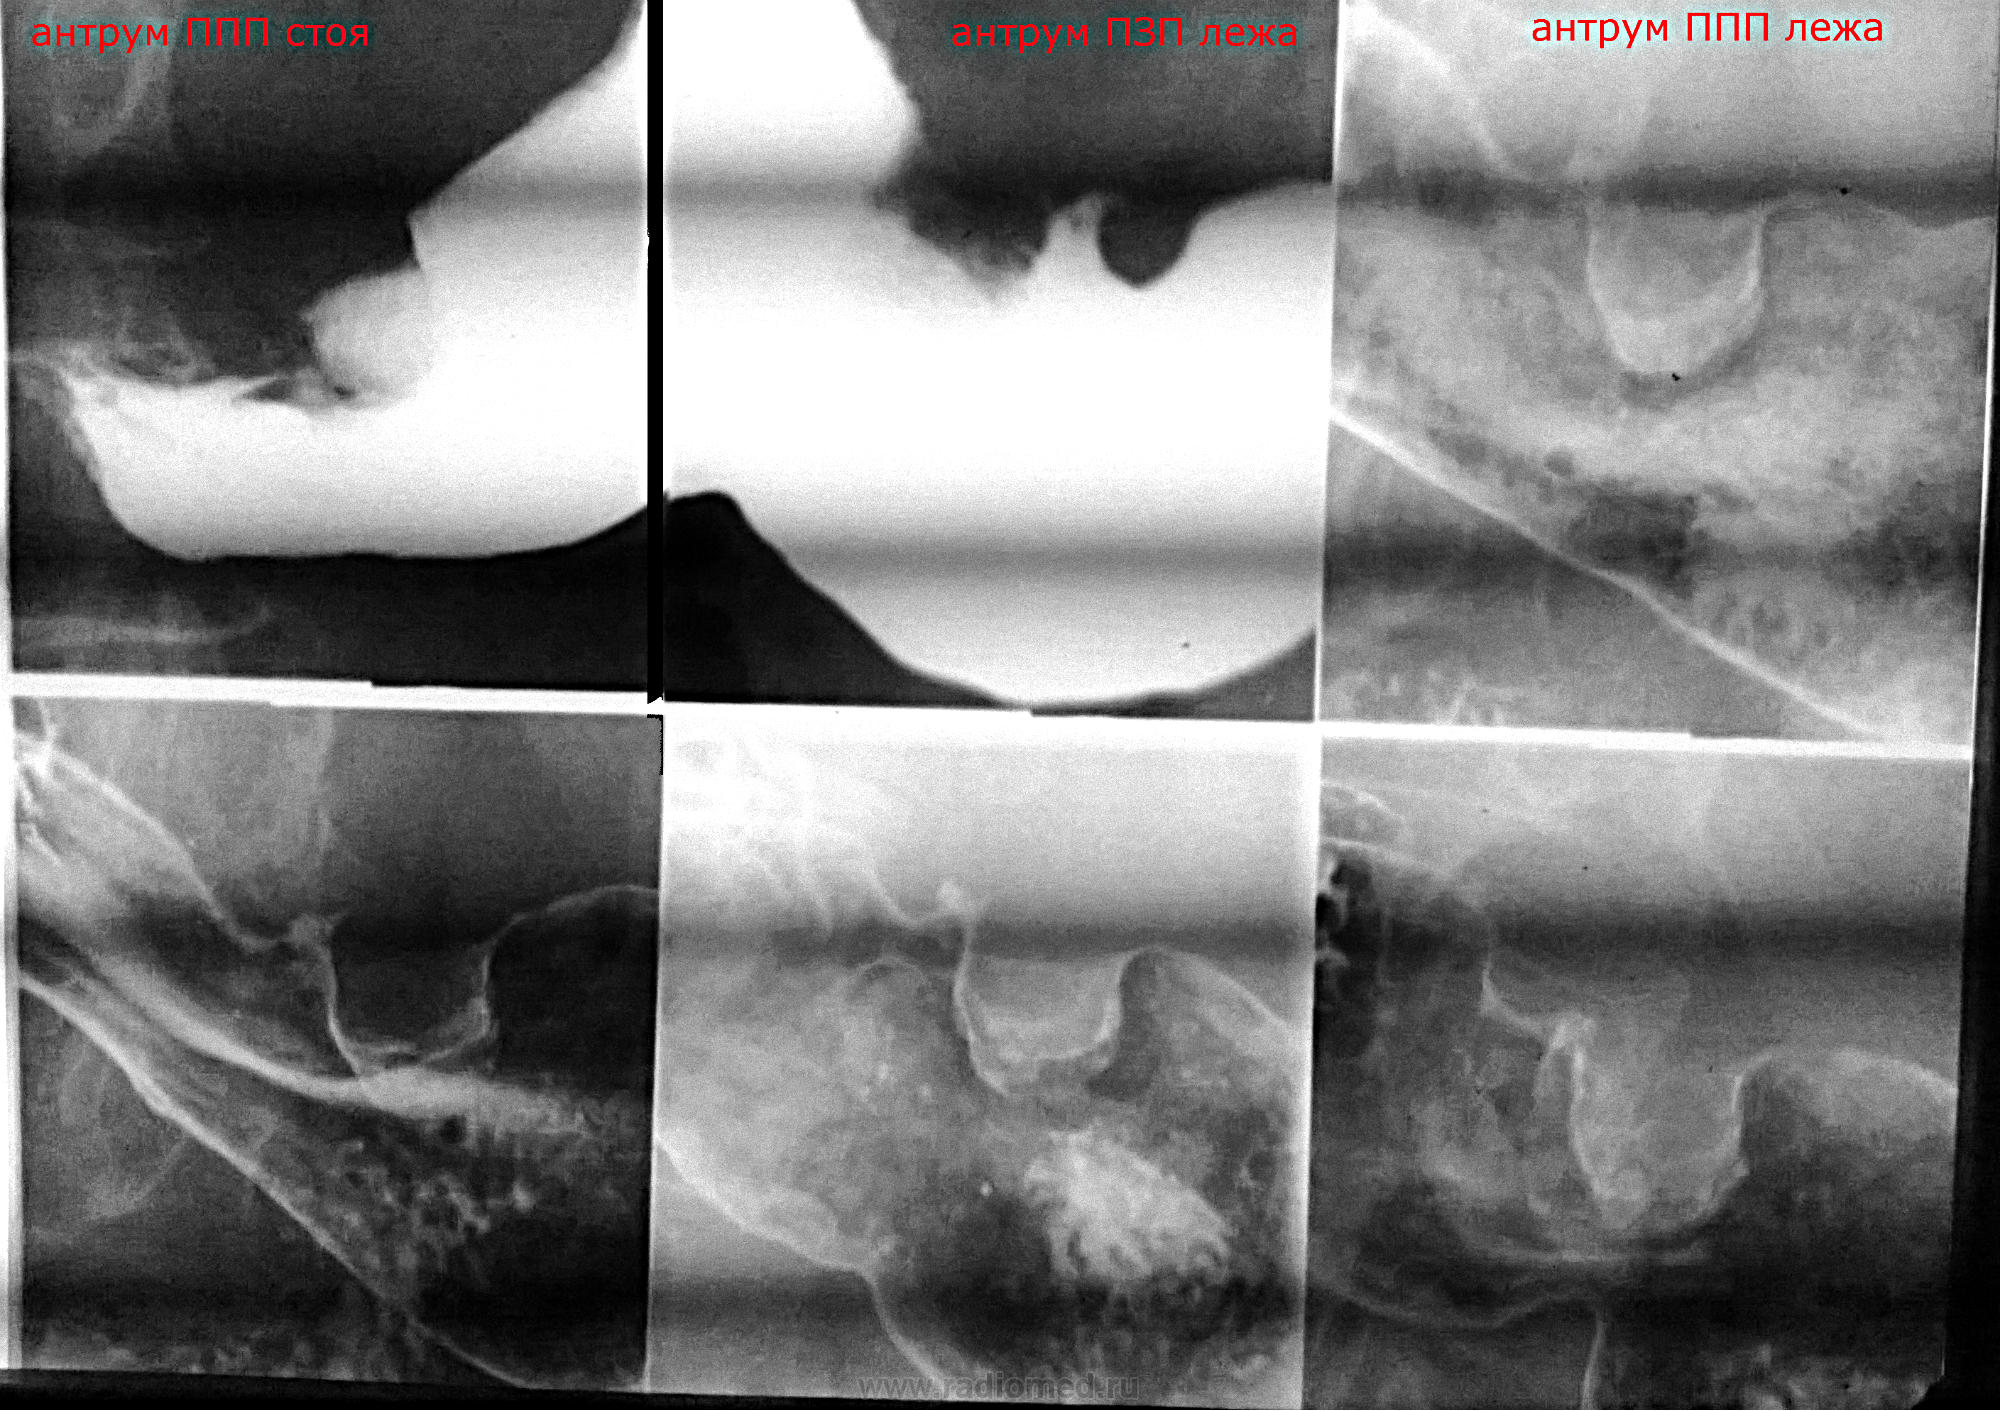

Мужчина 1963 г.р. Обратился с гастралгией к терапевту впервые за 15 лет (ранее по ФЭГДС единожды была язва малой кривизны тела желудка). Выполнена ФЭГДС (экзофитное бугристое серо-розовое плотное новообразование угла и малой кривизны антрума с рыхлой поверхностью, сплош покрытой детритом и белям налетом). Цитология - детрит, сплош мицелий грибка. Гистология отдана на руки (к онкологу). На рентгеноскопии - это. Стенка в зоне "бугоров" ригидна, аперистальтична.

Прошу прощения за полосы: частота матрицы камеры телефона на частоту ламп негатоскопа дает бегущую стриарность во всех положениях.

Рентгенологически экзофитный рак. Но меня совсем сбивает с толку грибок в желудке...

Извиняйте за молчание - не каждый день, а то и месяц могу отдохнуть на сайте... Так как я узурпировал в своем районе всю рентгенологическую и эндоскопическую власть в своих одних руках, мое заключение всегда носит комплексный характер, то бишь сам себе вразрез идти не могу. Посему эндоскопически: экзофитное новообразование угла желудка с распадом, подозрение на желудочный рак; рентгеноскопически: suspitio c-r antri ventriculi, смешанная форма роста. Suspitio - потому что без окончательной верификации.